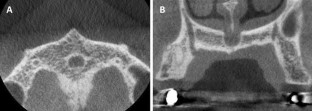

Fig. 4